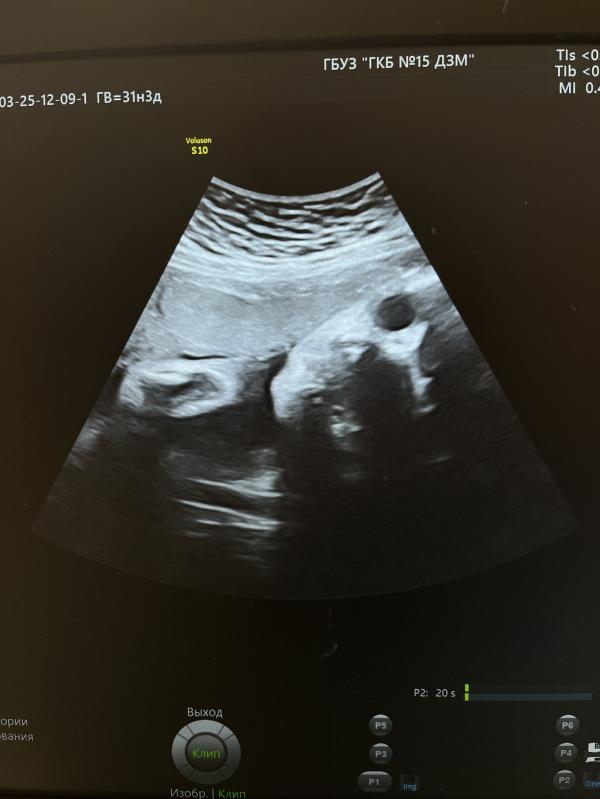

3 скрининг пройден

Вес 1755 +/- 256 гр

ЧСС 150 уд. в минуту

На 9 см выше внутреннего зева

Если еще почитать протокол УЗИ врача, то она пишет «В продольном положении в головном предлежании» и про пуповину «петель достаточное количество»